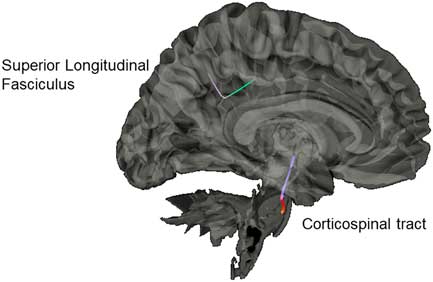

However, few studies have assessed longitudinal effects of altered DTI parameters in SRC. Lancaster et al. (2016) found acute differences in DTI metrics 24 hr after SRC that continued to become even more widespread by 8-days post-SRC. Murugavel et al. (Reference Murugavel, Cubon, Putukian, Echemendia, Cabrera, Osherson and Dettwiler2014) found similar acute differences, but at 2-weeks post-SRC found no differences in DTI metrics between college athletes with SRC and controls. Across these studies several white matter tracks have been implicated, including corpus callosum, corticospinal tract (CST), internal capsule, superior longitudinal fasciculus (SLF), and inferior longitudinal fasciculus (Gardner et al., Reference Gardner, Kay-Lambkin, Stanwell, Donnelly, Williams, Hiles and Jones2012, for review). These findings emphasize the need to study SRC separately from other forms of mTBI to assess DTI changes specific to athletes participating in youth sports.

Diffusion Group Connectometry Results

Results from the connectometry analyses revealed significant differences in isotropic diffusion between the control and SRC groups at time 1, with the SRC group showing increased isotropic value of the diffusion orientation density function along a segment of the CST (FDR=0.20) and the SLF (FDR=0.27; Figure 4). No significant correlations were found between neurocognitive performance on the ImPACT or TSS and diffusion metrics. No significant differences were seen between the control group and the SRC group at time 2.

Fig. 4 Significant difference in isotropic diffusion between the control group and SRC group at time 1, with the SRC group showing greater diffusivity in the corticospinal tract and the superior longitudinal fasciculus compared to the control group.

Our group connectometry analysis revealed disrupted diffusion within the CST and the SLF at time 1 in the SRC group compared to the control group. The CST and SLF have been consistently found to be altered in mTBI, and negatively correlated with clinical measures of severity of injury (e.g., Glasgow Coma Scale; Gardner et al., Reference Gardner, Kay-Lambkin, Stanwell, Donnelly, Williams, Hiles and Jones2012). Disruption of diffusion of the CST acutely post-SRC is hypothesized to be due to compressed intracellular space along the CST due to local inflammation and cytotoxicity (Henry et al., Reference Henry, Tremblay, Tremblay, Lee, Brun, Lepore and Lassonde2011; Virji-Babul et al., Reference Virji-Babul, Borich, Makan, Moore, Frew, Emery and Boyd2013).

With regard to the SLF, our results indicate the utility of the GQI approach to being more sensitive to dense white matter areas with crossing fibers, as our results indicated differences in a directional change of the SLF. This identified segment is part of the posterior portion of the SLF as it bends inferiorly from frontal lobe projections toward the tempo-parietal junction, and then branches to project toward the IPL, specifically the supramarginal gyrus. This is a centrally localized junction of several other white-matter tracks as well, including the arcuate fasciculus and posterior cingulum. This area has been reported in other studies to be particularly vulnerable to the linear (i.e., coup- contrecoup) injury and rotational forces that can damage the integrity of the crossing fibers in this dense area (Cubon, Putukian, Boyer, & Dettwiler, Reference Cubon, Putukian, Boyer and Dettwiler2011; Churchill, Caverzasi, Graham, Hutchison, & Schweizer, Reference Churchill, Caverzasi, Graham, Hutchison and Schweizer2017).

Overall our diffusion results are in line with our rs-fMRI results, which found specific positive correlations between cognitive performance and rs-fMRI within the IPL (including supramarginal gyrus) at time 1 and time 2. It is likely that activity in the IPL, in addition to negative modulation of frontal regions (SFG, MFG), may reflect disruption of white matter tracks between these regions known to be vulnerable to injury.